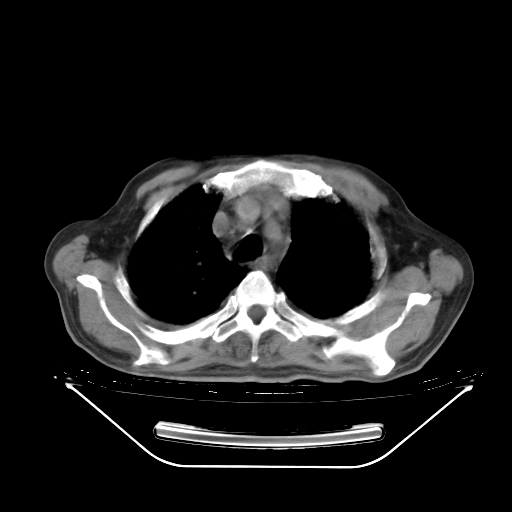

5月9日肺部CT(在4月27日齐鲁医院肺部CT描述部分肺组织磨玻璃样改变,12天后肺组织广泛磨玻璃样改变)

2009年5月9日肺部CT

大致读了系列胸部CT:纵隔窗无明显异常,肺窗:从4、27至今:主要是双肺中下野外带可见毛玻璃样改变,目前处于急性肺泡炎阶段,至于原因考虑1、结替组织或胶原血管性疾病所致?2、恶性疾病如恶组在肺部所致的表现或细支气管肺泡癌?3、药物或其它原因如肺蛋白沉着症所致肺泡炎目前不太可能?总之,明天就去请我院的呼吸科、感染科、血液科和临免专家会诊哈。